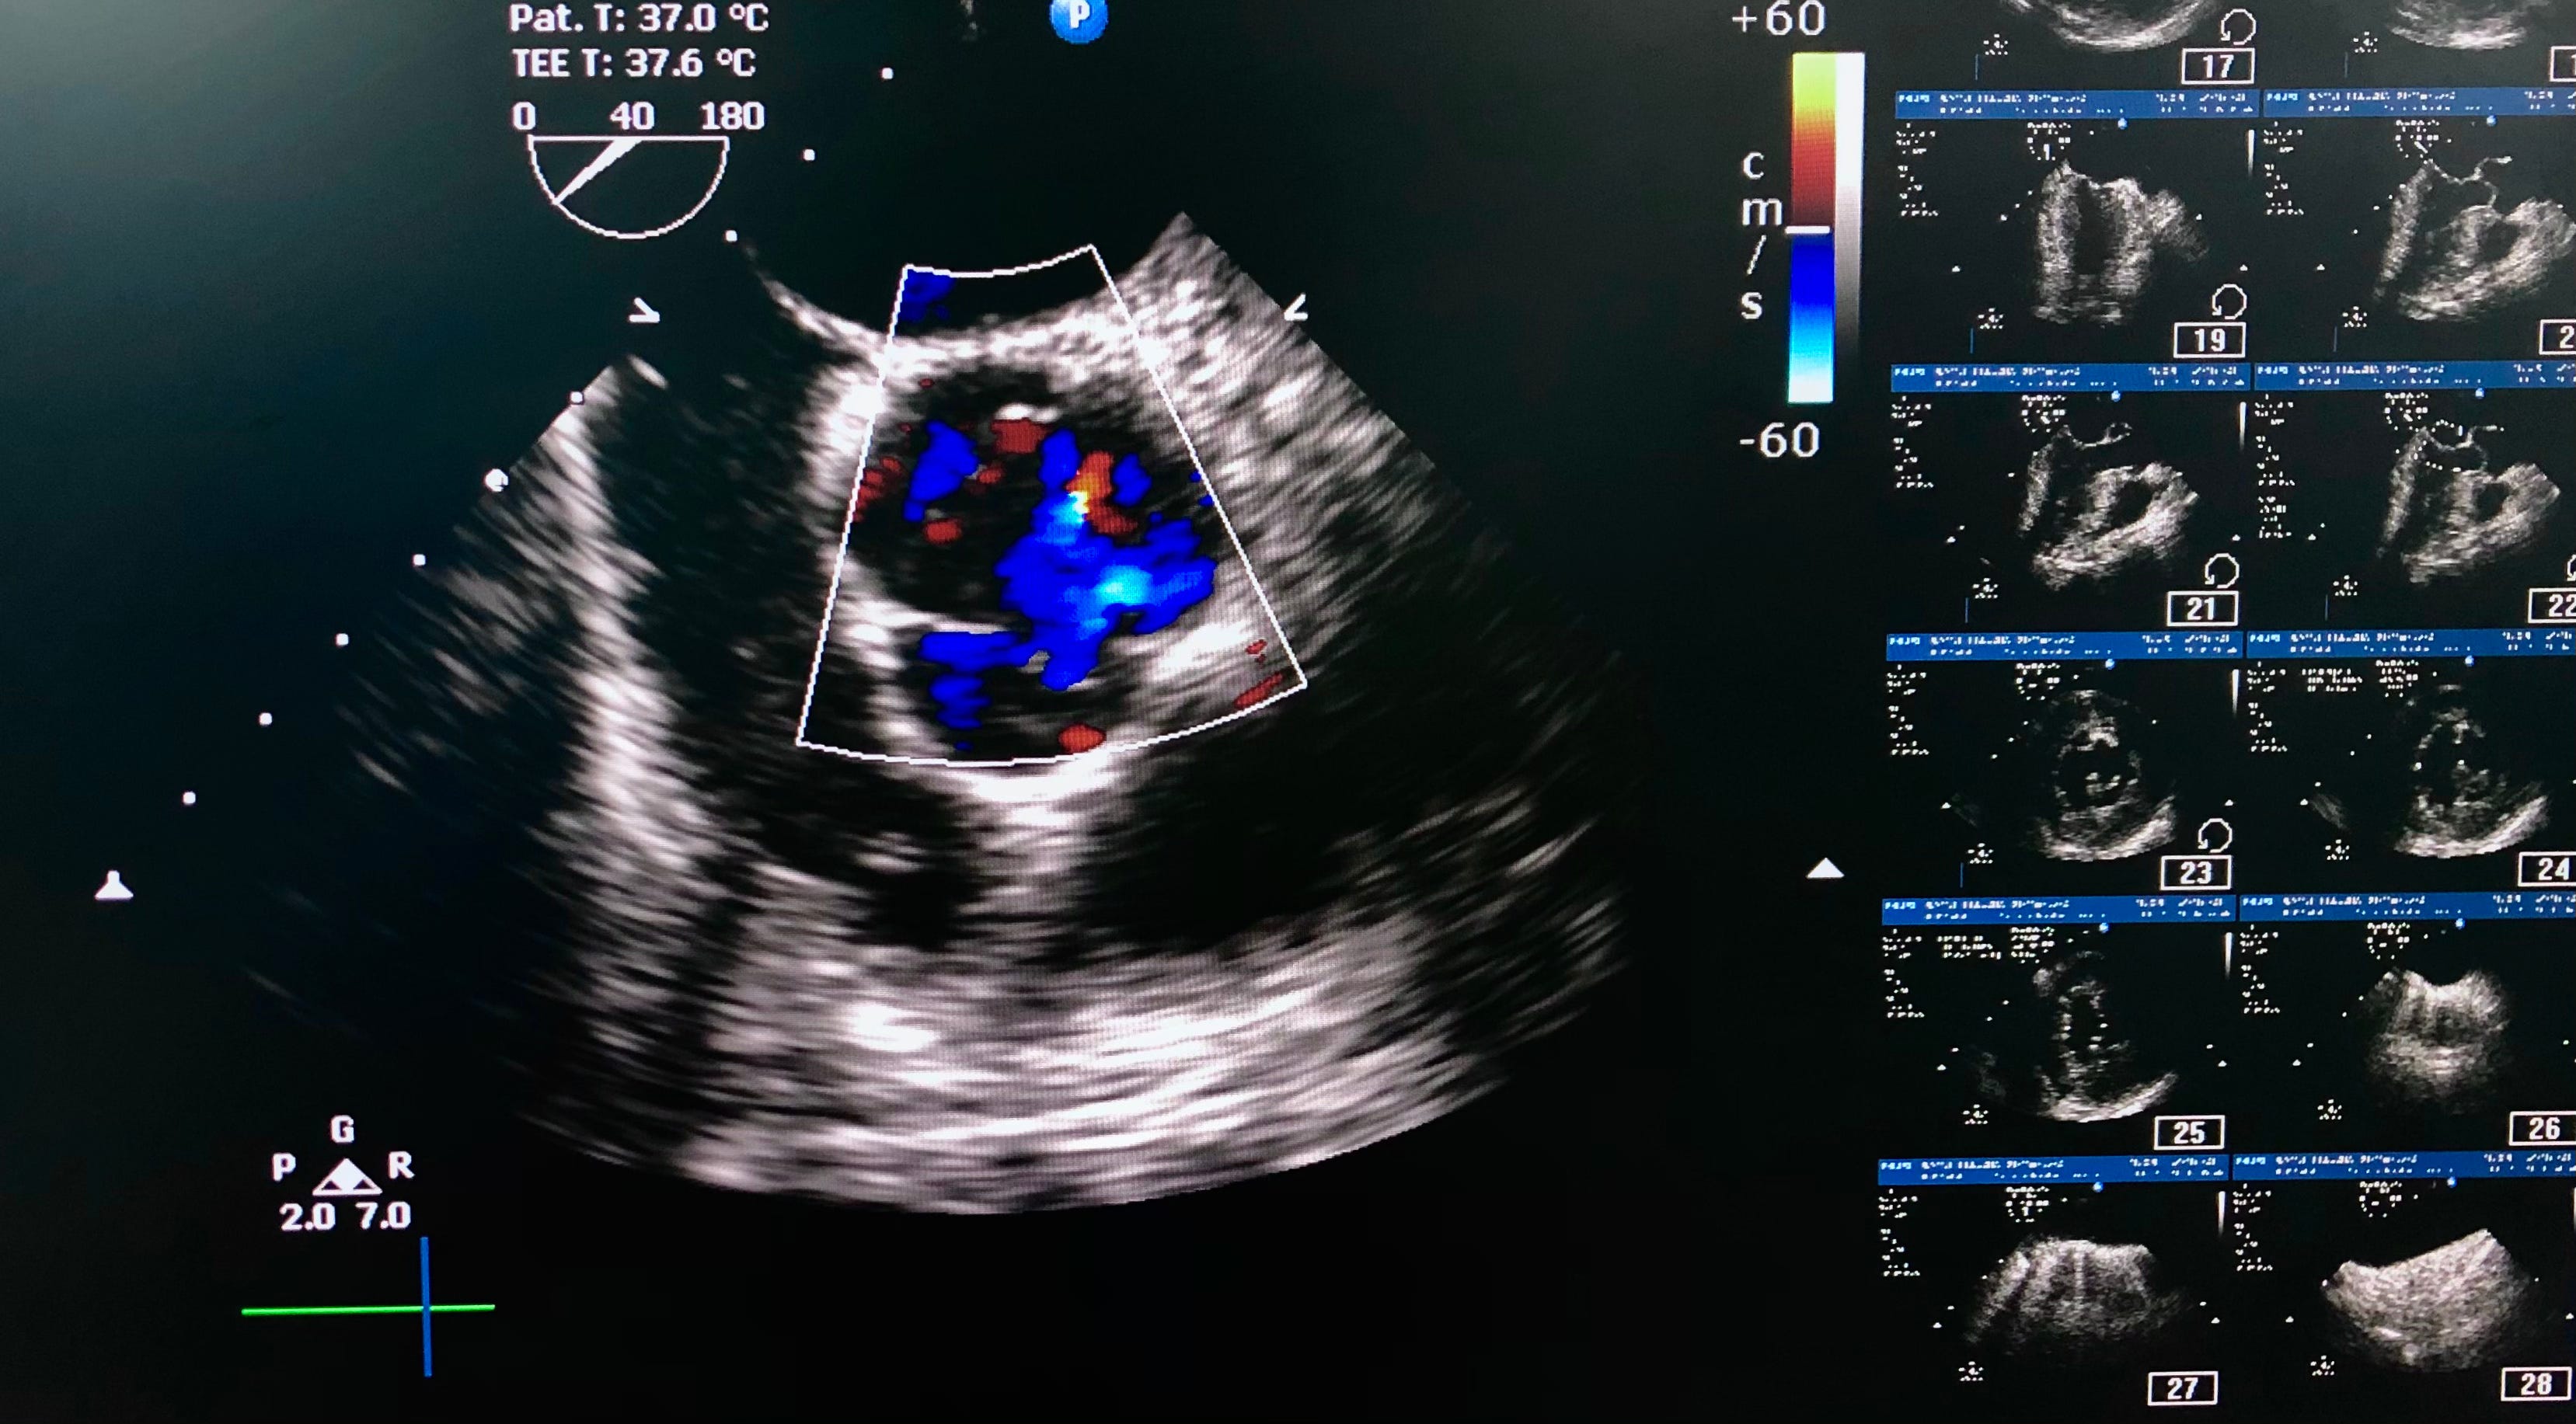

Resuscitative transesophageal echocardiography means using point-of-care TEE in emergency or critical care settings to guide treatments of crashing patients based on observed cardiovascular physiology in real-time. As TEE requires the insertion of…